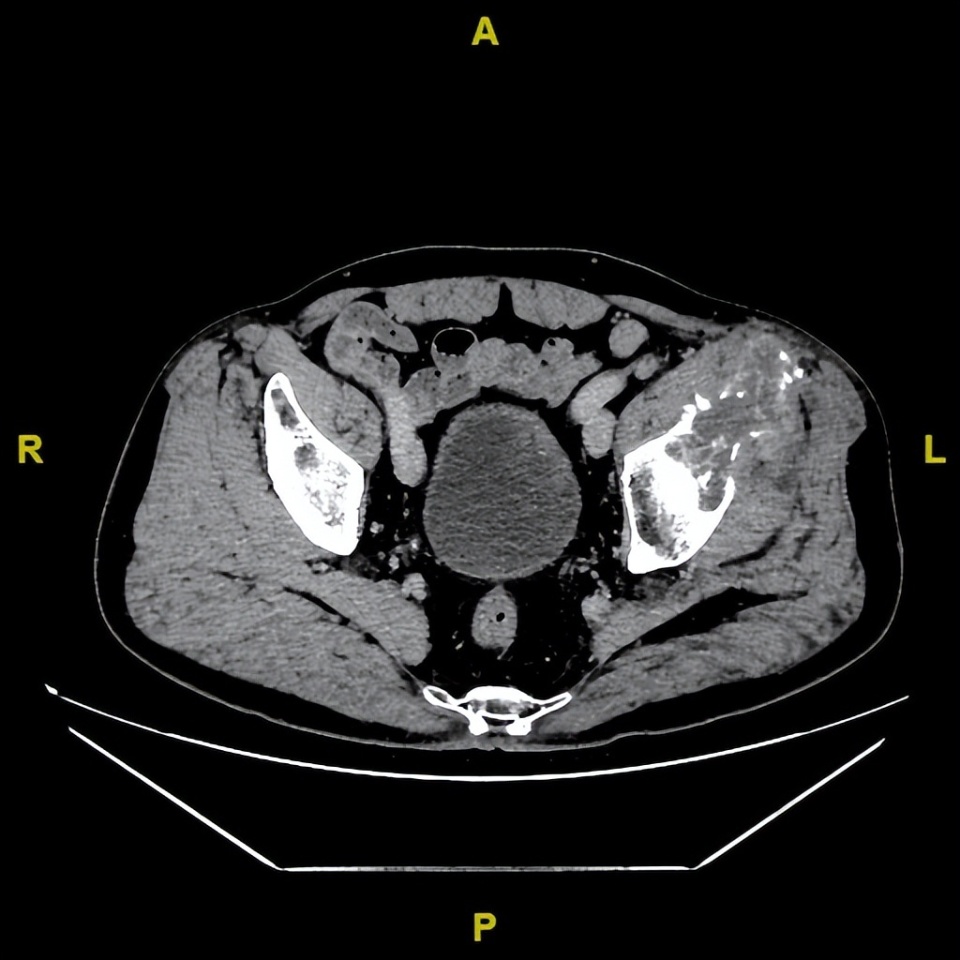

胸部CT(2022-12-13)平扫+增强:双肺转移;左侧髋关节CT:左侧髂骨见片状溶骨性骨质破坏,周围软组织肿胀,考虑骨转移。

基线(2022年12月13日)

△基线胸部CT和盆腔CT髂骨病灶